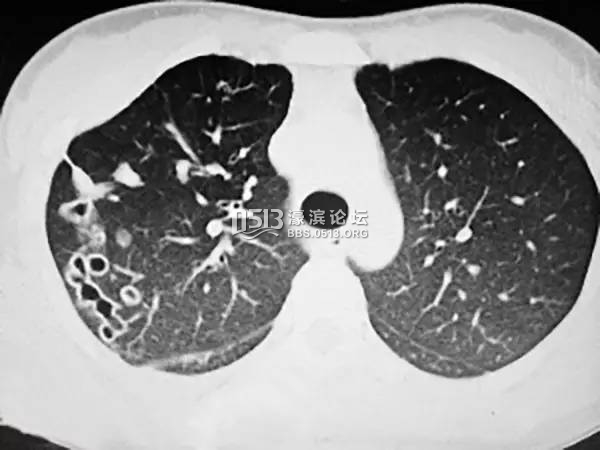

接诊医生徐主任在拿到小叶的肺部CT片子后,发现小叶右肺上有明显的“隧道”,弯弯曲曲好几条。看起来并不像是一般结核病或者支气管炎患者的片子。对于肺吸虫病有过诊断经验的徐主任便问及小叶的饮食喜好,小叶回答,自己喜欢生吃河海鲜,尤其醉虾醉蟹。9 r! d2 O) I( i1 R& B; f J; T

4 X+ e1 [) E F9 D/ G ]) P “从她的影像报告,结合喜欢生吃螃蟹这一点,我估计肺里有寄生虫,不过还需要进一步的证据,”徐主任联系了杭州市疾控中心,让小叶做了吸虫抗体原检测,检查结果证实了徐主任的判断:小叶得了肺吸虫病。; M7 D y# d R; U

' S0 [4 V; m$ l2 x肺吸虫留下的“隧道”成永久创伤

最后,徐主任为小叶开具了抗肺吸虫的药物,小叶恢复很快。不过遗憾的是,从此以后肺上的这些“隧道”会永久留下,肺纤维化,功能减弱,咯血可能还会出现,并且更容易受到感染。